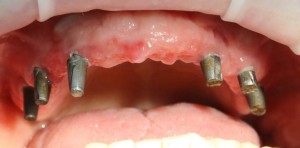

и, периодически, мне приходится видеть пациентов с базальными имплантами:

Как правило, вся работа с этими имплантами сводится к их удалению:

Затем — восстановление утраченных объемов костной ткани и нормальная, винтовая имплантация.